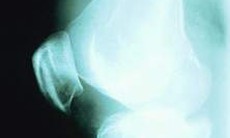

- Chỉ định chụp Xquang thông thường và xạ hình xương: để xác định tổn thương đốt sống nhưng không xác định được tổn thương tủy sống.

Sau khi khám lâm sàng ở bệnh nhân có tiền sử đang điều trị ung thư khác, ở người bệnh đang mắc ung thư các bác sĩ sẽ chỉ định kiểm tra trong đó sẽ chỉ định chụp cộng hưởng từ toàn bộ cột sống gồm cột sống cổ, ngực, thắt lưng cùng… giúp xác định vị trí và cấu trúc khối u di căn cột sống, giúp xác định mức độ chèn ép tủy và tổn thương tủy nếu có.